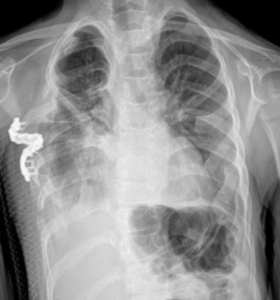

You observe how the right lung expands compared to the left side of the lung (operated side) on the lung X-ray graph of the patient whose right half of the thorax was expanded by applying lateral thoracic expansion.